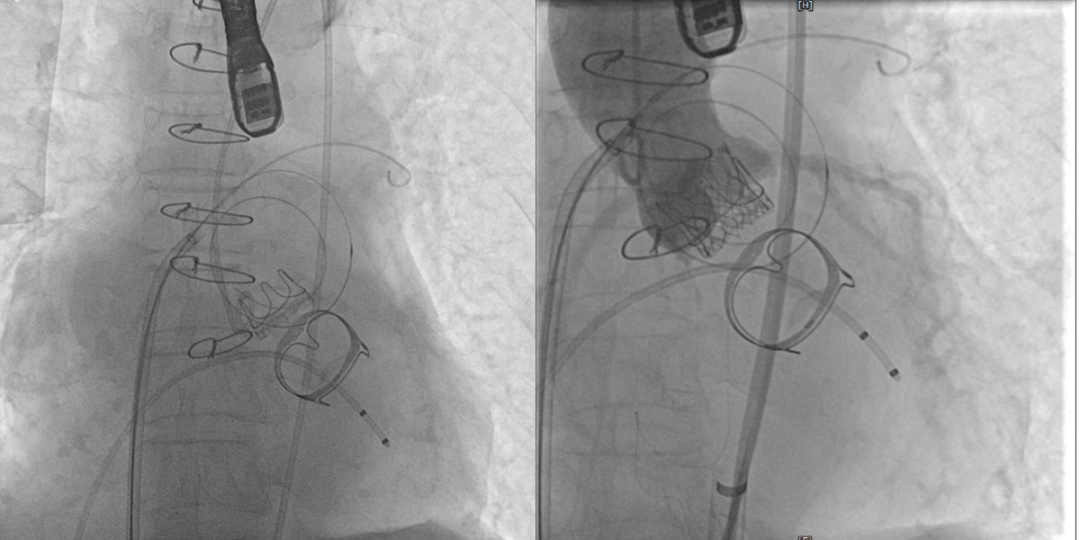

术前(图1)和TAVR 植入(图2)

在经过术前CTA评估测量等检查后,正式手术在珠海市人民医院医疗集团的百级层流复合手术室内进行,在林阿姨全麻的情况下使用食道超声及X线监测指引,经过3小时的紧张手术,双瓣中瓣手术最终成功完成。